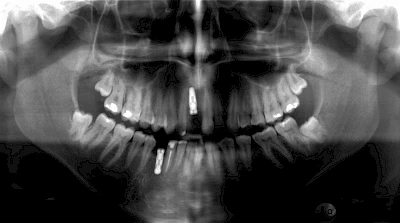

Damit Implantate an der richtigen Stelle im Kieferknochen platziert werden könen, gibt es heute vielfältige Möglichkeiten der Planung. In vielen Situationen kann die Erfahrung des Zahnarztes ausreichend sein.

Nicht selten ist jedoch auch eine technisch aufwändigere Vermessung im Vorfeld sinnvoll, z. B.:

- Wenn sich der Kieferknochen abgebaut hat

- Wenn der Nervverlauf im Unterkiefer beachtet werden muss

- Wenn die Ausdehung der Kieferhöhle im Oberkiefer beachtet werden muss

- Wenn wenige Restzähne keine gute Orientierung erlauben

In diesen Fällen kann die Planung mittels verschieden aufwendiger Röntgen-Techniken (Übersichtsaufnahme, DVT) ggf. unter Zuhilfenahme speziell angefertigter Planungsschablonen sinnvoll sein.